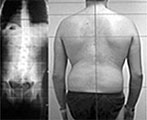

Beispiele, wie sich die Haltung unter der posturologischen Therapie zum Positiven verändert:

Behandlung von Haltungsschäden

Vor der Behandlung steht eine Analyse der Haltungsgewohnheiten und -fehler.

Dabei wird der ganze Körper fotografiert und vermessen. So erkennt man auch die sonst nicht wahrnehmbaren Schwankungen, mit denen der Mensch sich in Balance hält. Anhand der gespeicherten Daten kann man später die Fortschritte messen.

Selbst Jahrzehntelange Fehlentwicklungen werden korrigiert

Auch im fortgeschrittenen Alter kann man mit Posturologie die Haltung noch ändern und somit Fehlentwicklungen korrigieren.

- Verkrümmte Wirbelsäulen gebessert oder wieder gerade

zu Beginn der Behandlung und nach 12 Monaten